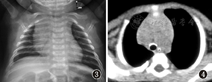

胸部X线显示气管-支气管钙化影(图3);胸部CT+呼吸道三维重建提示符合肺炎CT表现,气管软骨钙化表现(图4);超声心动图未查。患儿对声音刺激反应敏感,未行脑干诱发电位检查。院外痰培养2次,培养出卡他布兰汉菌及草绿色链球菌。血清钙正常,其他血液化验检查基本正常。由于患儿家长拒绝,未行相应基因检测。